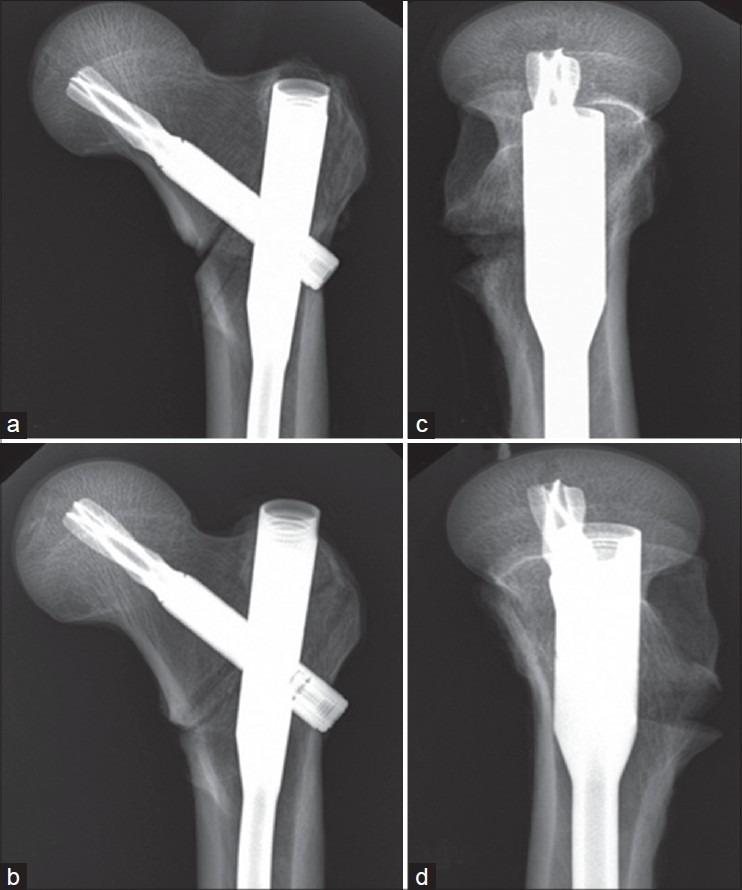

Despite new developments in the management of osteoporotic fractures, complications like screw cutout are still found in the fixation of proximal femur fractures even with biomechanically proven better implants like proximal femoral nail antirotation (PFNA). The purpose of this cadaveric study was to investigate the biomechanical stability of this device in relation to two common positions (center-center and inferior-center) of the helical blade in the femoral head in unstable trochanteric fractures.

Eight pairs of human cadaveric femurs were used; in one group [center-center (C-C) group], the helical blade of PFNA was fixed randomly in central position both in anteroposterior and lateral view, whereas in the other group it was fixed in inferior one-third position in anteroposterior and in central position in lateral view [inferior-center (I-C) group]. Unstable intertrochanteric fracture was created and each specimen was loaded cyclically till load to failure

Angular and rotational displacements were significantly higher within the C-C group compared to the I-C group in both unloaded and loaded condition. Loading to failure was higher in the I-C group compared to the C-C group. No statistical significance was found for this parameter. Correlations between tip apex distance, cyclic loading which lead to femoral head displacement, and ultimate load to failure showed a significant positive relationship.

The I-C group was superior to the C-C group and provided better biomechanical stability for angular and rotational displacement. This study would be a stimulus for further experimental studies with larger number specimens and complex loading protocols at multicentres.